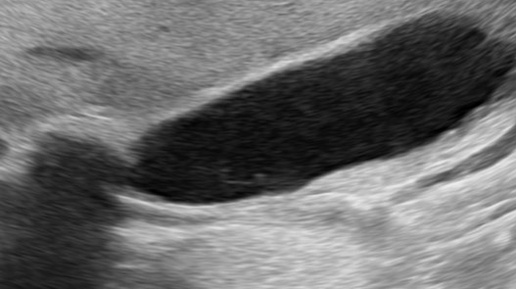

Блокирующий конкремент в шейке желчного пузыря (УЗИ)